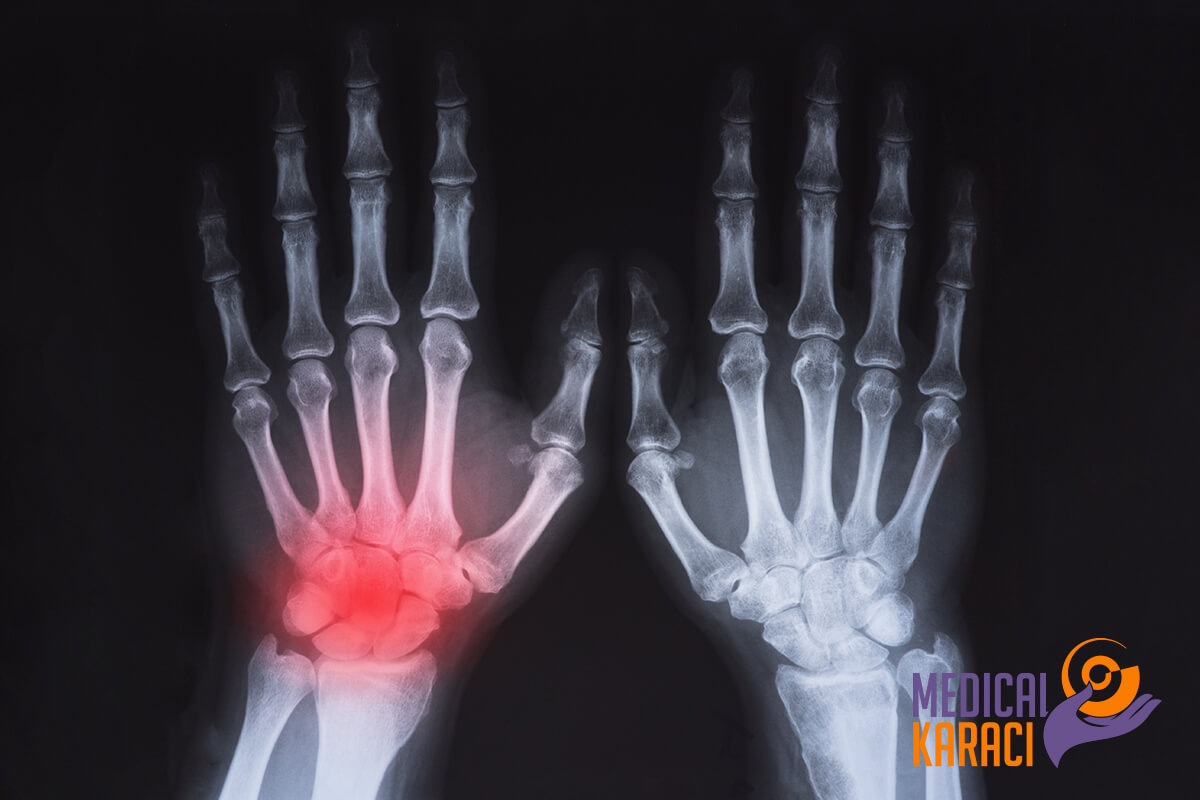

ARTRITE REUMATOIDE

L'artrite reumatoide è una malattia infiammatoria cronica che può colpire non solo le articolazioni. In alcune persone, la condizione può danneggiare un'ampia varietà di sistemi corporei, tra cui la pelle, gli occhi, i polmoni, il cuore e i vasi sanguigni.

A differenza dei danni da usura dell'osteoartrite, l'artrite reumatoide colpisce il rivestimento delle articolazioni, causando un gonfiore doloroso che può portare all'erosione delle ossa e alla deformazione delle articolazioni.

- L'artrite reumatoide precoce colpisce di solito le articolazioni più piccole, soprattutto quelle metacarpo-falangee e metatarsali. Con il progredire della malattia, i sintomi si estendono spesso a polsi, ginocchia, caviglie, gomiti, fianchi e spalle. Nella maggior parte dei casi, i sintomi si manifestano nelle stesse articolazioni, simmetricamente su entrambi i lati del corpo.